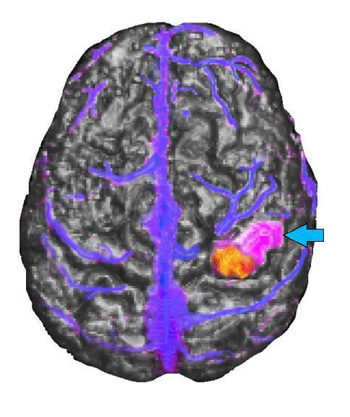

Representación triple

El neurocirujano tiene una vista restringida del cerebro a través de la pequeña ventana de la craneotomía. Las técnicas de obtención de imágenes neurológicas modernas pueden mostrar la anatomía en tres dimensiones, y en una ventana mucho más grande.

Caso 1

Mujer diestra de 27 años de edad sometida a IMR y VRM para descartar una lesión estructural. La paciente se ofreció voluntariamente para realizar una tarea de generación de verbos.

Imagen de representación triple. Vista lateral izquierda de IRM, VRM e IRMf

La imagen muestra la fusión de los tres procedimientos diferentes. La representación volumétrica del cerebro obtenida de la secuencia de IRM se observa en una escala de grises. La imagen de las venas superficiales y el seno del hemisferio izquierdo obtenida mediante la VRM se observan en color azul. La activación obtenida de la secuencia ecoplanar usada para la IRMf se muestra en color amarillo y rojo.

Caso 2

Niña diestra de 15 años de edad con convulsiones sensoriales motoras parciales que involucran la mano izquierda desde los 5 años de edad. La IRM mostró una anomalía de señal focal en la circunvolución postcentral derecha como consecuencia de un tumor en desarrollo sin cambios durante un período de 2 años.

Vista de representación triple sagital media superior

La IRM del cerebro aparece en una escala de grises, la activación por RM funcional se muestra en amarillo y rojo, el tumor se ve de color púrpura (flecha celeste) y las venas, de color azul. El tumor aparece localizado en la circunvolución postcentral de forma lateral y rostral con respecto a la activación funcional. La relación entre el tumor y la activación funcional fue confirmada durante el mapeo intraoperativo con el paciente despierto. Los puntos de referencia venosos proporcionaron información útil al cirujano que realiza la intervención. Se extirpó el tumor de la paciente sin monoplejia residual. La paciente solo presentó pérdida temporal de estereognosis y propiocepción relacionada con el tercer, cuarto y quinto dedo, después de la cirugía.